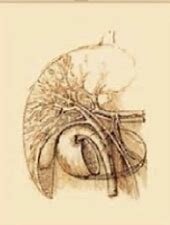

• primer trasplante en animales

El primer trasplante fue realizado en un animal, y el órgano trasplantado fue un riñón.

Se llevo a cabo por Freerick Grant, Charles Best, James Collip y J.J.R

• Primer trasplante de humano

Primer trasplante realizado a un ser humano, el órgano trasplantado fue un riñon